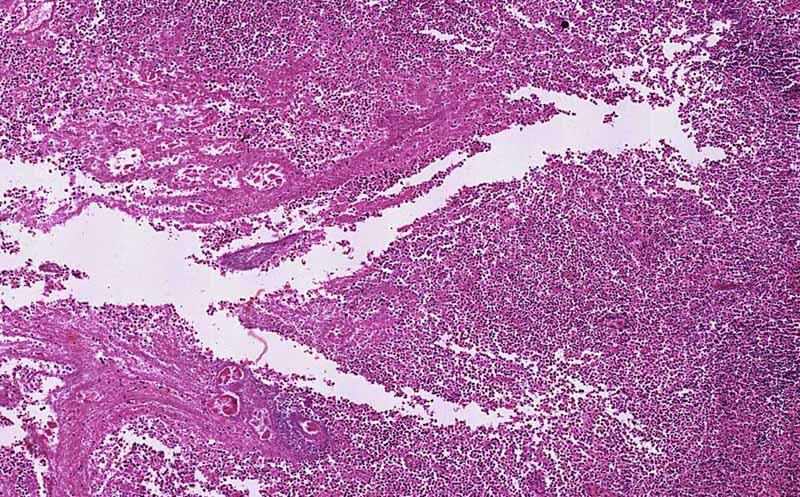

Hematoxylin & eosin

Area 1: The general outline of the lymphocytes of the normal appendix as well as the shape of the appendiceal lumen can still be recognized. On higher magnification, you can see that many of the cells are not viable. Numerous necrotic cells are present.